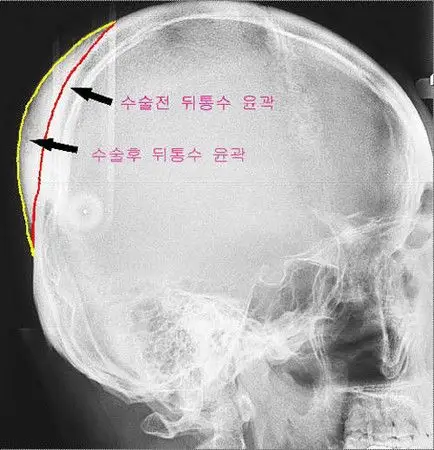

韩国「后脑勺整形手术」 现在还有什麼不能整呢.